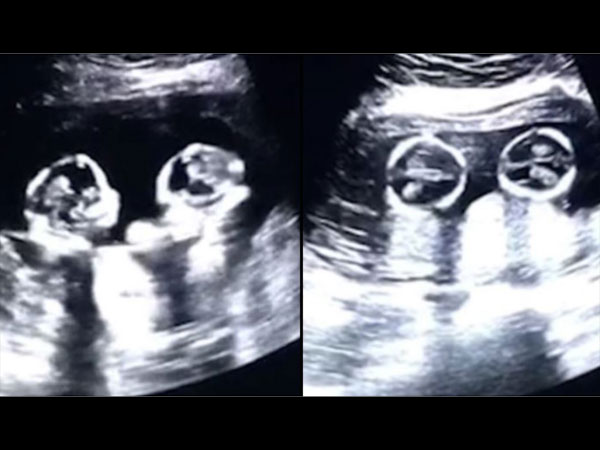

अल्ट्रासाउंड में दिखी गर्भ में जुड़वां बच्चों की लड़ाई, वीडियो हुआ वायरल

गर्भ में जुड़वां बच्चों की खबर सुन कर किसी भी मां बाप को बहुत खुशी होगी लेकिन तब आप कैसी प्रतिक्रिया देंगे जब आपको मालूम चले कि इस दुनिया में कदम रखने से पहले ही उन बच्चों ने गर्भ में ही लड़ना शुरू कर दिया है? सुनने में ये काफी अजीब लगेगा। यहां हम एक वीडियो शेयर कर रहे हैं जिसमें जुड़वां शिशु स्कैन के दौरान एक दूसरे से दो दो हाथ करते दिखे। इस लेख के माध्यम से आप भी देखें वो वीडियो।

सूत्रों के मुताबिक ये वीडियो पिछले साल का है जिसे चीन के एक व्यक्ति ने अपनी प्रेगनेंट पत्नी के अल्ट्रासाउंड के दौरान रिकॉर्ड किया। महिला के गर्भ में जुड़वां बच्चियां थी और अल्ट्रासाउंड के वक्त वो चार महीने पूरे कर चुकी थीं।

अल्ट्रासाउंड स्कैन में नजर आया कुछ अलग

अल्ट्रासाउंड स्कैन वीडियो में दोनों भ्रूण एक दूसरे को लात और हाथ से मारते हुए नजर आए। पिता ने सोशल मीडिया पर इस वीडियो को शेयर किया और देखते ही देखते ये वायरल हो गया।